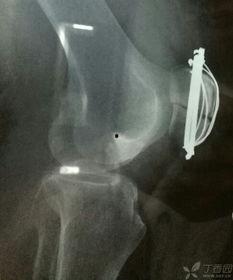

首先,咱们得弄明白什么是髌骨骨折。髌骨,也就是我们常说的膝盖骨,是人体最大的籽骨,位于膝盖前方。它连接股骨和胫骨,起到稳定膝关节的作用。髌骨骨折,就是膝盖骨断裂了,这种情况可能是因为跌倒、撞击或者剧烈运动造成的。